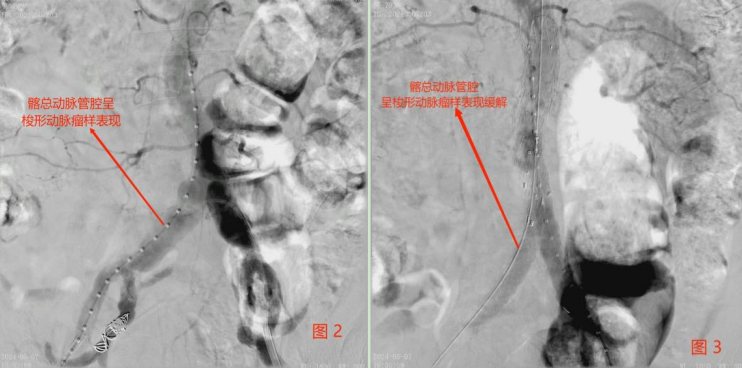

判断患者具有明确手术指征、无手术禁忌证后,科室迅速完善术前准备,拟行手术治疗。术前造影可见右侧髂总动脉管腔呈梭形动脉瘤样表现(见图2)。随时有可能出现破裂大出血,经血管外科专家团队讨论后。遂决定行髂动脉支架植入术。支架顺利植入右侧髂动脉内,瘤样扩张缓解(见图3)。患者术后回复良好,已康复出院。